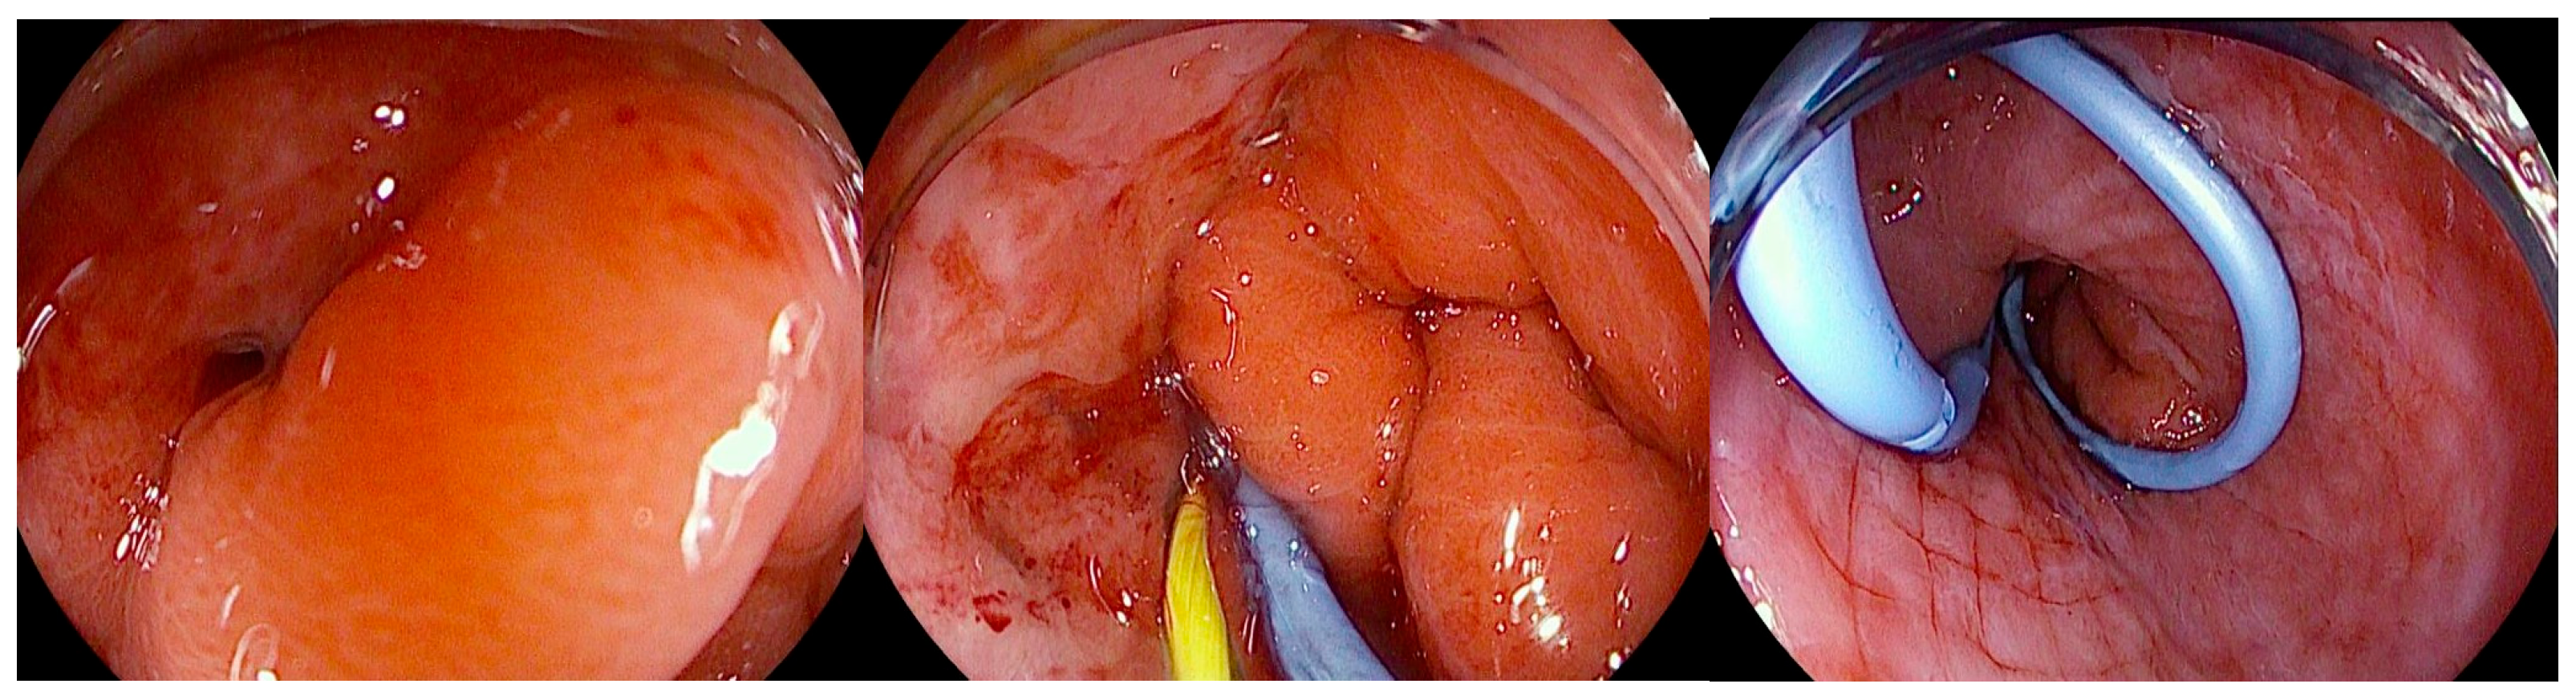

Figure 6.

Endoscopic view of a gastric fistula after sleeve gastrectomy communicating with a perigastric cavity, showing the transfistulous endoscopic placement of a 0.035 Fr radiopaque guidewire followed by deployment of a double-pigtail plastic stent. The copyright of this figure belongs to the authors.